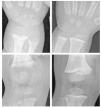

La primera etapa se caracteriza por osteopenia e hipocalcemia subclínica o evidente (por lo general muy transitoria y, por ello, no documentada), que se sigue en la segunda etapa por valores crecientes de PTH. Los aumentos de PTH provocan la movilización del calcio del hueso y la corrección de la hipocalcemia. La matriz de colágeno desmineralizada es propensa a la hidratación y la tumefacción, lo que causa que la cobertura perióstica se expanda hacia fuera, y provoque dolor óseo mediado por las fibras sensoriales periósticas del dolor. En la última etapa, las alteraciones óseas se hacen más intensas y la hipocalcemia vuelve a ser evidente. Los síntomas de raquitismo pueden oscilar de ninguno a grados variables de irritabilidad, retraso del desarrollo motor grosero y dolor óseo. Los signos incluyen el ensanchamiento de las muñecas y los tobillos, el genu varo o valgo, la prominencia de las uniones condrocostales (rosario raquítico), el retraso del cierre de las fontanelas, la craneotabes y el abombamiento frontal. La erupción dentaria puede ser tardía, y el esmalte puede ser de mala calidad, la deficiencia de vitamina D se produce in utero o al principio de la lactancia, lo que aumenta el riesgo de caries. El raquitismo también puede asociarse con un mal crecimiento (manifestación de la enfermedad ósea asociada) y una mayor susceptibilidad a las infecciones. La deficiencia de vitamina D que se presenta como convulsiones hipocalcémicas o tetania se notifica con mayor frecuencia en la lactancia y la adolescencia que en la infancia. En estos períodos de mayor velocidad de crecimiento, la mayor demanda de calcio no puede cubrirse de forma adecuada, y el paciente puede presentar una hipocalcemia incluso antes de la aparición de desmineralización ósea o de signos radiológicos de raquitismo21,22. Durante la infancia, las menores demandas metabólicas permiten que el organismo evite la hipocalcemia sintomática recurriendo a los depósitos óseos de calcio secundarios al hiperparatiroidismo en la segunda etapa de la enfermedad. No obstante, se produce a expensas de vaciar de calcio al hueso, provocando signos de desmineralización y posterior deformidad ósea22. Los niños hipocalcémicos con deficiencia de vitamina D pueden presentar rasgos clínicos asociados con la propia hipocalcemia, como episodios de apnea, estridor o sibilancias, hipotonía, debilidad muscular e hiperreflexia. La intensa deficiencia de vitamina D también puede estar asociada con una miocardiopatía relacionada con la hipocalcemia, que se normaliza con el tratamiento23. El diagnóstico de raquitismo depende de la presencia de los rasgos clínicos antes mencionados y de aspectos radiológicos y de laboratorio. Las imágenes radiológicas pueden indicar osteopenia y adelgazamiento cortical de los huesos largos, fracturas de estrés y ensanchamiento y desflecado metafisario. El signo más temprano suele ser la osteopenia, seguida del ensanchamiento de la placa de crecimiento por la proliferación de cartílago y osteoide no calcificados, seguidos del ensanchamiento, la separación, el acopamiento y el desflecado metafisario (fig. 1). Se observa un basto patrón trabecular de la metáfisis. La alteración raquítica más temprana es la pérdida de separación entre la metáfisis y la placa de crecimiento, así como la pérdida de la zona provisional de calcificación20. Se ha desarrollado un índice radiológico de diez puntos como ayuda para valorar la gravedad del raquitismo, basado en los hallazgos en la rodilla y la muñeca24 (tabla 2). Los hallazgos de laboratorio consisten en hipofosfatemia, grados variables de hipocalcemia, aumento de las fosfatasas alcalinas y aumento de los valores de PTH. Los bajos valores de 25(OH)-D confirman el diagnóstico, pero pueden no ser necesarios cuando los demás hallazgos clínicos, radiológicos y de laboratorio son inequívocos. Los valores de 1,25(OH)2- D pueden aumentar conforme se elevan los valores de PTH con incremento concomitante de la actividad de la 1- alpha;-hidroxilasa. La tabla 1 resume los hallazgos de laboratorio en las tres etapas del raquitismo por deficiencia de vitamina D25.

Fig. 1. Raquitismo por deficiencia de vitamina D a la presentación (arriba) y tres meses después del tratamiento con vitamina D y calcio (abajo) en un niño de raza negra de un año de edad. A la presentación, las radiografías de la muñeca (izquierda) y la rodilla (derecha) mostraron separación, acopamiento desflecado y desmineralización de las metáfisis distales del cúbito y el radio, la metáfisis distal del fémur y las proximales de la tibia y el peroné. Después del tratamiento, el niño mostró la resolución casi completa del desflecado metafisario con desarrollo de una densa zona provisional de calcificación en la metáfisis, compatible con la curación del raquitismo.